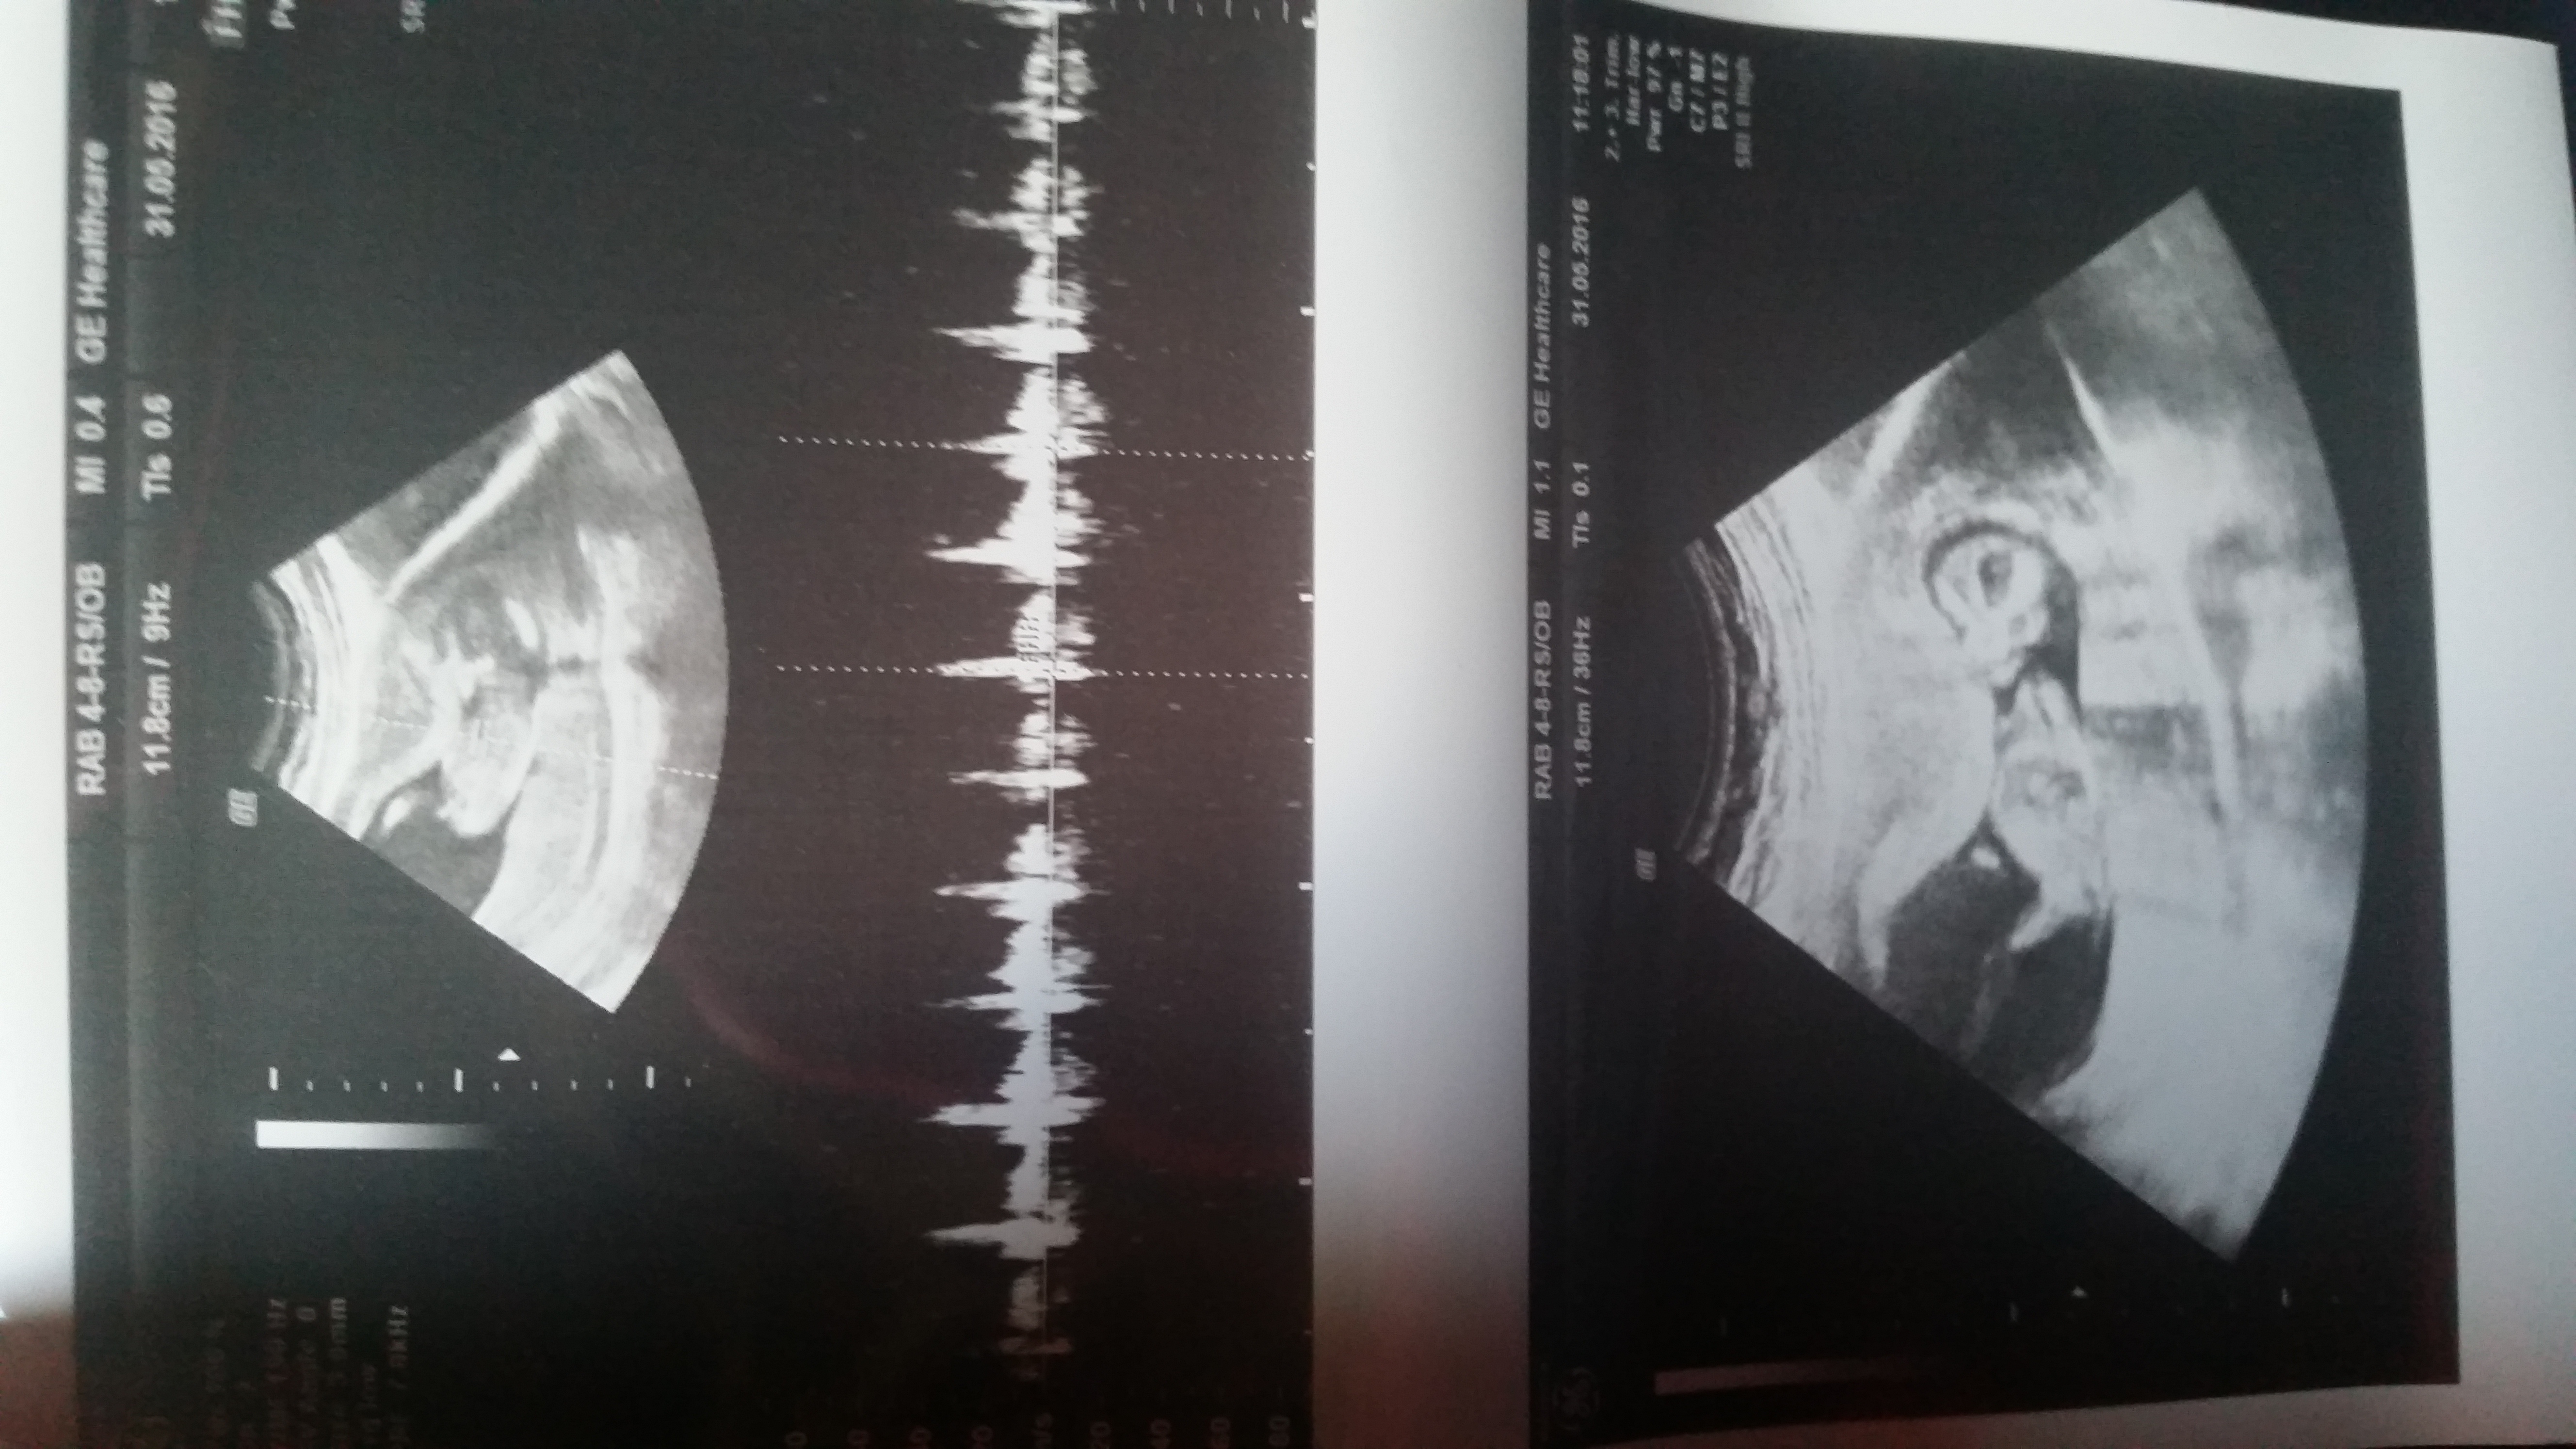

Currently 13 wks.. any guesses will be appreciated... thank you!!!

Attachment 31559

Here are other shot.. thanks!!!!

If that's the nub I'm seeing in the first pic then boy.

I believe so.. I asked the dr if it was a leg and she said no and zoomed in so I could take a better look... :)

I also think boy

Boy guess.